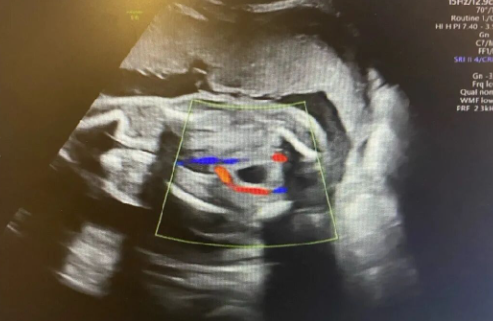

【↑节目中提到的脐动脉栓塞真实照片】